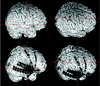

Fig 3.

Subdural strip and double strip electrodes and their relationship to the Sylvian fissure (left) and to the precentral gyrus (right).